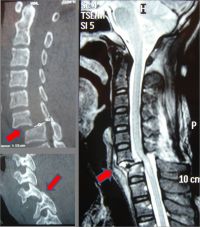

颈椎骨折MRI

重物从7楼砸下来,刚好砸到头部(其他的伤势暂且不论),头部是靠颈椎支撑的,这大多数造成颈椎骨折,尤其是造成骨折-脱位,这随时可以把藏在脊柱里面的脊髓横切断。横切断脊髓是什么概念?

高位截瘫,顾名思义,是指横贯性病变发生在脊髓较高水平位上(像桑兰、保安一样,都是颈部脊髓横断,高位)。颈髓损伤在颈5以上则引起四肢以及躯干的运动、感觉消退或消失,称高位截瘫。高位截瘫一般都会出现四肢瘫痪,预后多不良,其它方面跟下肢截瘫相同。脊柱椎骨或附件骨折,移位的椎体或突入椎管的骨片,可能性压迫脊髓马尾神经,使之发生不同程度的损伤,受伤脊髓横断平面以下,肢体的感觉运动、反射完全消失,膀胱、肛门括约肌功能完全丧失的,称完全性截瘫。颈段脊髓损伤后,双上肢有神经功能障碍者,为四肢瘫。